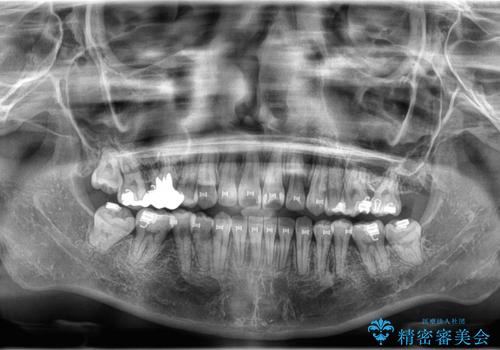

ワイヤー矯正を用いて、欠損部の閉鎖を目的とした後方からの歯の挺出・移動を行いました。

特に、親知らずを活用し、奥歯の噛み合わせを構築することに重点を置きました。

治療の途中で、1年間ご来院が難しい期間があり、当初の予定より治療期間は延長しましたが、

最終的には予定通りインプラントを使用せずに欠損部を閉鎖し、咬合も安定させることができました。